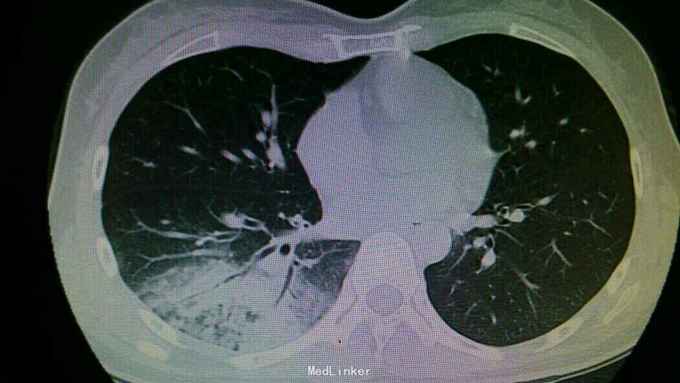

查体:右下肺可闻及湿性啰音。余无特殊。 辅查:右肺下叶大叶性肺炎。

诊断:大叶性肺炎。 治疗:入院予以抗感染,止咳化痰等治疗。